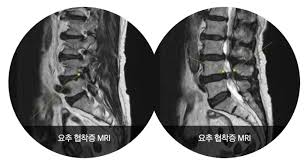

✅ 허리협착증이란?

허리협착증은 척추 속 신경이 지나가는 통로인 '척추관'이 좁아지면서, 신경을 눌러 통증이나 저림 등의 증상을 유발하는 질환입니다.

- 요추관협착증은 주로 허리 부분(L3~L5)의 협착으로 인해 발생합니다.